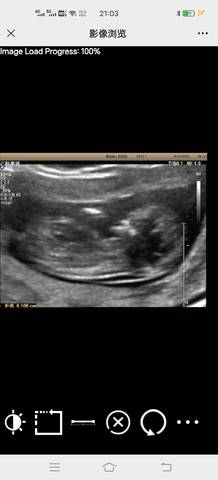

大家帮忙看一下能看出来是男宝还是女宝吗?

journal_insert_pic_1719798795

你好。根据数据图片看不出来的。是不科学依据的,孕期定期检查,只要宝宝健康就好。祝心想事成。

亲爱的,通过这些判断不出来的哈,反正宝宝发育好就是最好的哈,祝你心想事成。加油